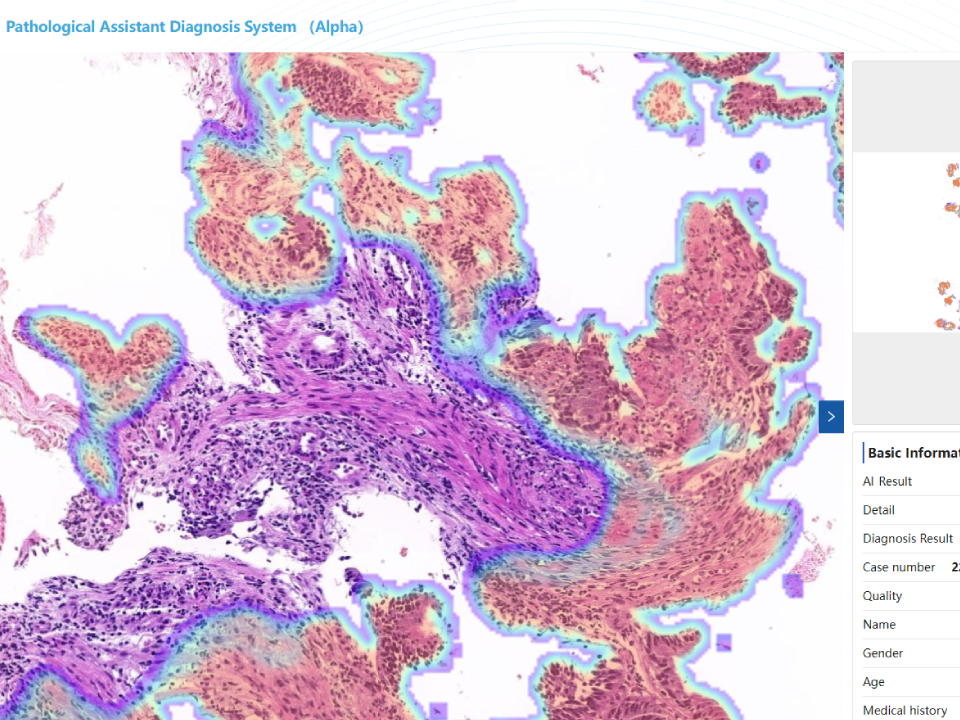

Gastric Biopsy Assistant Diagnostic Module

Efficient identification of tissue structural changes and cellular abnormalities. Automatically recognize eight lesion types,covering more than 95% of lesion types. Automatically capture the lesion area,effectively assist doctors in diagnosis. Combine pathology images, gastroscopy and medical history to improve physicians' diagnostic accuracy.

Intestinal Biopsy Assistant Diagnostic Module

Detection of small early lesion areas with high accuracy. Automatically recognize six lesion types,covering more than 95%of lesion types. Significantly shorten the diagnostic time and reduce workload. Combine pathology images,colonoscopy and disease history to improve diagnostic accuracy.

Cervical Biopsy Assistant Diagnostic Module

Whole slide analysis, automatic identification of squamous and adenocarcinomas Combine pathologicimages, colposcopy and medical history to improve diagnostic accuracy Combine diagnosis with cervical cytology diagnostic module,greatly improve the diagnostic accuracy of doctors.

Endometrial Biopsy Assistant Analysis Module

Fusion of high and low magnification models to discriminate tissue structural changes and cellular abnormalities. Rapid localization of lesions. Automatic recognition of six lesion types. Combining pathologic images and patient age to improve diagnostic accuracy.

Gastric Biopsy Assistant Diagnostic Module

Efficient identification of tissue structural changes and cellular abnormalities.

Automatically recognize eight lesion types,covering more than 95% of lesion types.

Automatically capture the lesion area,effectively assist doctors in diagnosis.

Combine pathology images, gastroscopy and medical history to improve physicians’ diagnostic accuracy.

Intestinal Biopsy Assistant Diagnostic Module

Detection of small early lesion areas with high accuracy.

Automatically recognize six lesion types,covering more than 95%of lesion types.

Significantly shorten the diagnostic time and reduce workload.

Combine pathology images,colonoscopy and disease history to improve diagnostic accuracy.

Cervical Biopsy Assistant Diagnostic Module

Whole slide analysis, automatic identification of squamous and adenocarcinomas

Combine pathologicimages, colposcopy and medical history to improve diagnostic accuracy

Combine diagnosis with cervical cytology diagnostic module,greatly improve the diagnostic accuracy of doctors.

Endometrial Biopsy Assistant Analysis Module

Fusion of high and low magnification models to discriminate tissue structural changes and cellular abnormalities.

Rapid localization of lesions.

Automatic recognition of six lesion types.

Combining pathologic images and patient age to improve diagnostic accuracy.